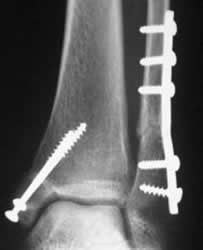

Fig 98. Tornillos de esponjosa.

A: Rx AP. Fractura espiroidea del fémur distal. Se encuentra tornillo de esponjosa en la tibia proximal (Solo roscado en la mitad distal), que fija fractura antigua.

B: Fractura bimaleolar, fijada con tornillos de esponjosa.